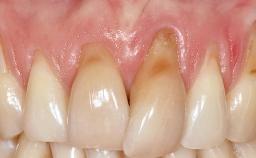

Treatment of Soft-Tissue Fenestration in the Esthetic Zone

This case demonstrates that a connective-tissue graft in combination with a coronally positioned graft is an effective method of treating cases with peri-implant mucositis and an abutment-level sinus abscess. A 42-year-old man presented with a swelling adjacent to an implant crown at site 21. The swelling had been present for approximately three weeks and was constrained to the buccal and palatal gingival aspects of the implant. A discharge was noted on finger pressure, with localized gingival recession present on the mid- and distolabial aspects of the crown.